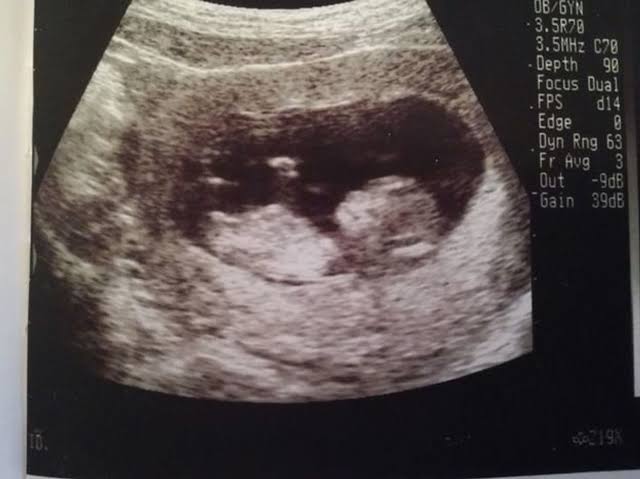

Ultrasound images allegedly used for fraud

These posts alleged that the images were being weaponised in scams: women would send them to men, claim to be pregnant, and demand cash to cover abortion costs.

One widely shared post on X claimed that such listings were customised with personal details such as names and dates, making the scam appear more convincing.

A listing detailing which details you can customise in the ultrasound purchase including name and date.